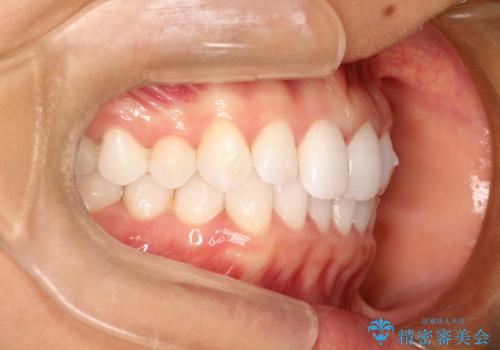

気になる前歯の歯並びをインビザラインで矯正

- 前歯の傾きと、ガタガタが気になるとのことで来院されました。

アスリートの方でしたので、競技に支障が少ないインビザラインで治療することとなりました。

前歯の傾きや高さをシミュレーションで患者様と確認しながら、歯並びを仕上げていきました。